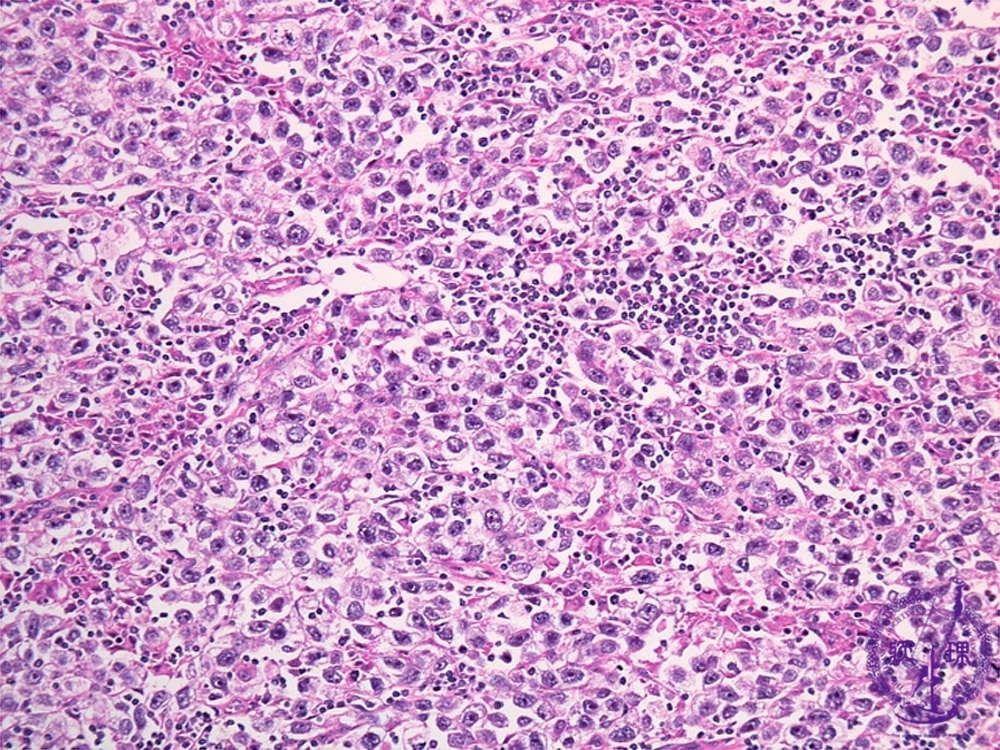

Histology (HE stain, intermediate power): Seminoma. Large rounded tumor cells have clear cytoplasm and glycogen in their cytoplasm.